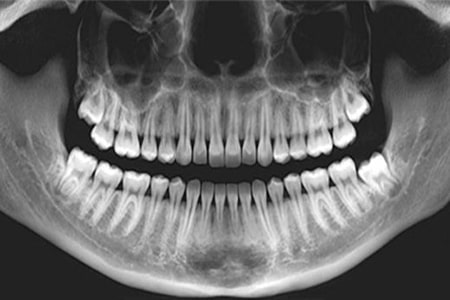

- عکس پانورامیک (کلی فک)؛ این عکس تصویری گسترده و جامع از کل دهان ارائه میدهد، شامل تمام دندانها، فک بالا و پایین، مفاصل فکی، سینوسها و دندانهای عقل. این تصویر نقش بسیار مهمی در برنامهریزی درمان ارتودنسی دارد.